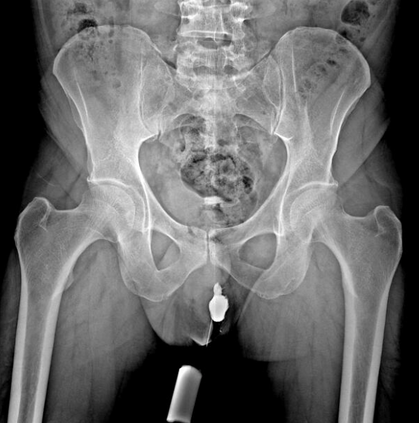

In this study, we aim to initiate the development of Radiology Foundation Model, termed as RadFM.We consider the construction of foundational models from the perspectives of data, model design, and evaluation thoroughly. Our contribution can be concluded as follows: (i), we construct a large-scale Medical Multi-modal Dataset, MedMD, consisting of 16M 2D and 3D medical scans. To the best of our knowledge, this is the first multi-modal dataset containing 3D medical scans. (ii), We propose an architecture that enables visually conditioned generative pre-training, allowing for the integration of text input interleaved with 2D or 3D medical scans to generate response for diverse radiologic tasks. The model was initially pre-trained on MedMD and subsequently domain-specific fine-tuned on RadMD, a radiologic cleaned version of MedMD, containing 3M radiologic visual-language pairs. (iii), we propose a new evaluation benchmark that comprises five tasks, aiming to comprehensively assess the capability of foundation models in handling practical clinical problems. Our experimental results confirm that RadFM significantly outperforms existing multi-modal foundation models. The codes, data, and model checkpoint will all be made publicly available to promote further research and development in the field.